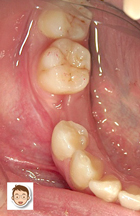

17才の女性。主訴は「乳歯が抜けたあと、永久歯が生えてきません」=写真左=でした。

まず、永久歯が生えてこない状態のことを「先天性の永久歯欠損」といいます。原因は、生まれつき大人の歯の数が少ないため、乳歯が抜けたあとに歯が生えてこないのです。このような場合、3通り(インプラント/ブリッジ/入れ歯)の治療方法があります。

まずは、インプラント治療。これならブリッジ治療のように、両サイドの白い歯を削る必要はありません。また入れ歯のような装着時の違和感もありません。「インプラント=ベストの選択」と言いたいところですが、この患者様の年齢(17歳)を考えますとインプラント治療の時期はまだ早い(あご骨が成長途中のため)と考えられます。

残り、「ブリッジ」と「入れ歯」のどちらを選択すればいいのでしょうか?